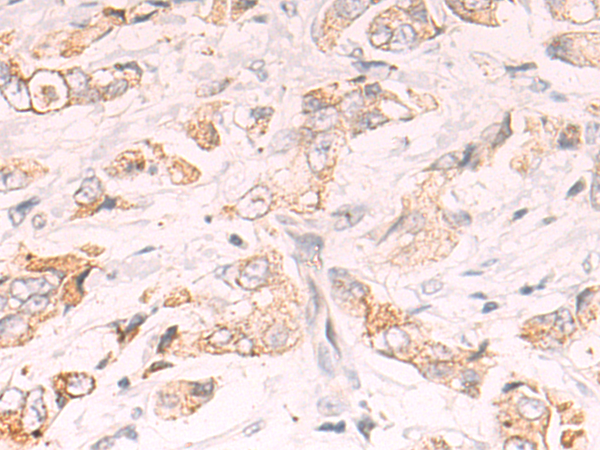

分类: 科研抗体货号: P04198别名: R16; AAAT; ATBO; M7V1; RDRC; ASCT2; M7VS1应用: IHC反应种属: Human